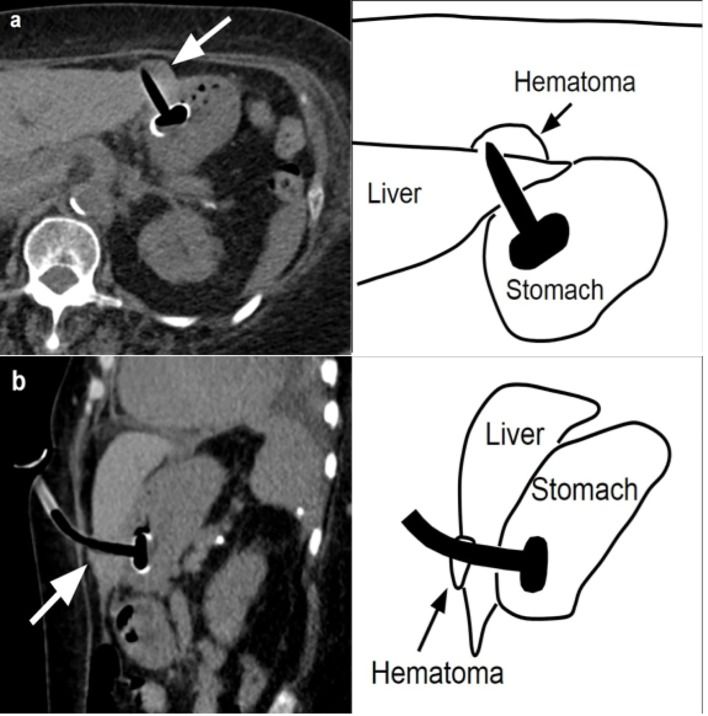

Чрескожная эндоскопическая гастростомия в настоящее время — стандарт в обеспечении пациента энтеральным питанием на длительное время. Осложнения при данном вмешательстве редки, одно из чрезвычайно редких — повреждение печени.

Авторами из США описано[1], как в результате установки 78-летней пациентке гастростомы трубка прошла через ткани печени. В анамнезе у больной — инсульт, сахарный диабет 2-го типа, гипертония и ожирение (индекс массы тела — 34 кг/м2), а показанием для гастростомии стали нарушения глотания.

В ходе процедуры пациентка лежала на спине. Проведенная после вмешательства КТ брюшной полости показала, что гастростомическая трубка пересекла боковой край печеночного сегмента 3 с прилегающей гематомой размером 2 × 2 × 4 см (рис. 1).

Рисунок 1 [1].

При обследовании брюшной полости трубка PEG свободно вращалась, зона вмешательства была чистой и сухой — без крови и наличия содержимого. Уровень гемоглобина оставался стабильным. Энтеральное питание начали вводить через 24 часа после процедуры без осложнений. Пациентка была выписана.